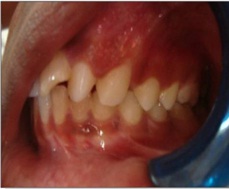

A 22-year-old male patient reported to the Out Patient Department at Sharad Pawar Dental College, Wardha with the chief complaint of swelling on the left side of the face since 2-3 months. There was history of fractured 21 due to bicycle accident. The patient was fine initially, after one month he experienced pain and sensitivity which increased on taking cold beverages and relived on its withdrawal; after which he noticed pea sized swelling on the palatal surface and then reported for the same to our hospital. On extra oral examination a diffuse swelling was observed which was ill-defined in nature [Table/Fig-1]. On intraoral examination Ellis class II fracture was seen in relation to 21 [Table/Fig-2].

Intraoral view showing factured 21

A swelling was seen on the bucco-gingival area extending upto the palatal surface in relation with 21 which was approximately 0.5x0.5cm, oval in shape having colour same as that of adjacent mucosa [Table/Fig-3]. On the basis of clinical evaluation we arrived to a provisional diagnosis of Radicular cyst with 21. Several investigations were carried out in order to obtain a confirmatory diagnosis namely, IOPA which was suggestive of a well-defined radiolucent line involving 21,22,23,24,25 appearing radiolucent in nature & an occlusal radiograph suggestive of the same [Table/Fig-4a,b].

Intraoral view showing site of lesion